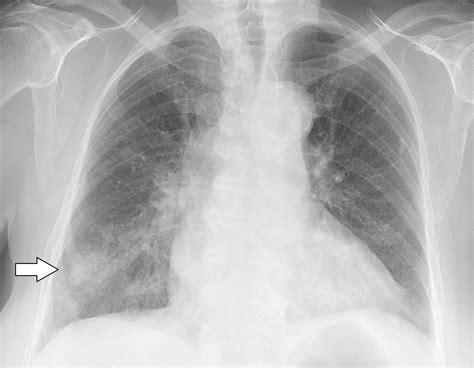

When to See a Doctor

Although the condition is mild, it should not be ignored. You should seek medical attention if you experience difficulty breathing, a persistent high fever, or if your cough worsens significantly. A healthcare provider can perform a physical examination, listen to your lungs, and potentially order a chest X-ray or a lab test to confirm the diagnosis. Early intervention can help manage symptoms more effectively and reduce the time you remain infectious to others.